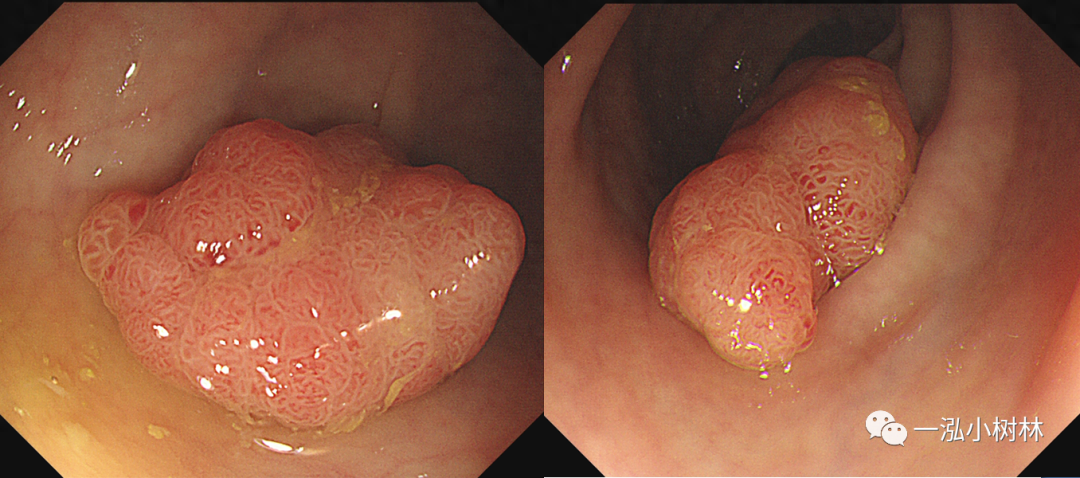

图1 结肠管状腺瘤(JNET2A型)